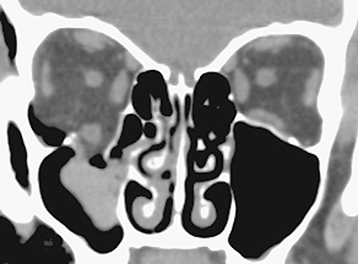

Figure 14.2.2: Coronal soft tissue window shows a large blowout fracture of the right orbital floor.

This finding was missed on the axial study in Figure 14.2.1, demonstrating the importance of reviewing both axial and coronal images.

Figure 14.2.3: Coronal bone window of the patient seen in Figure 14.2.2 shows the fracture again.

In bone windows, the soft tissue detail fades, but bone detail is enhanced, allowing for better examination of bony anatomy.